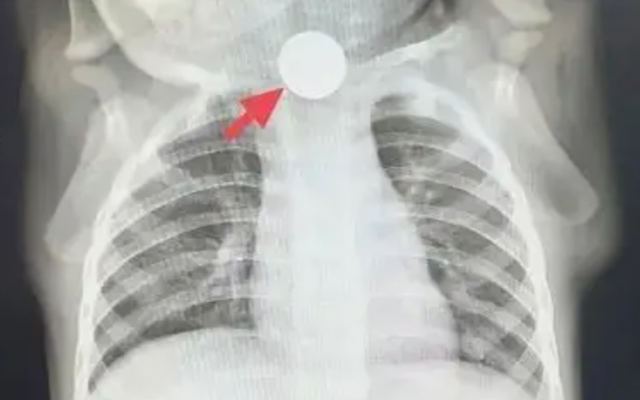

“Không thể chủ quan được, trước tiên cho bé chụp X-quang ngực để loại trừ vấn đề ở phổi!” - bác sĩ dặn gia đình. Thế nhưng, kết quả phim chụp mang lại không phải sự yên tâm, mà là một phát hiện khiến mọi người giật mình: ở đoạn trên thực quản của Đông Đông, có một đồng xu mắc kẹt!

Sự thật lập tức sáng tỏ: cái gọi là “chán ăn” thực chất là đồng xu mắc ở thực quản gây đau, khiến bé không thể ăn uống bình thường; chảy nước dãi là do dị vật chặn lại, nước bọt không nuốt xuống được; ho là phản xạ khi nước bọt tràn vào đường thở. Chẩn đoán trước đó là “chán ăn do ảnh hưởng tâm lý” hoàn toàn là nhận định sai lầm!

“Trẻ bị mắc một đồng xu trong thực quản đã gần một tuần, cần chuẩn bị nội soi lấy dị vật ngay!”. Sau khi nhận được thông báo khẩn, ê-kíp nội soi nhanh chóng vào vị trí, chuẩn bị kỹ lưỡng trước thủ thuật. Khi ống nội soi dạ dày được đưa vào, có thể thấy rõ đồng xu mắc ngang trong thực quản. Vùng niêm mạc xung quanh đã bị viêm đỏ, sưng phù, thậm chí xuất hiện ổ loét sâu, liên tục rỉ máu. Các bác sĩ thao tác hết sức cẩn trọng, chính xác gắp lấy đồng xu. Toàn bộ quá trình diễn ra trong không khí căng thẳng nhưng trật tự, cuối cùng đồng xu cũng được lấy ra thành công. Nhìn đồng xu vừa được gắp ra, bố mẹ Đông Đông vừa đau lòng vừa nhẹ nhõm, liên tục nắm tay bác sĩ cảm ơn.